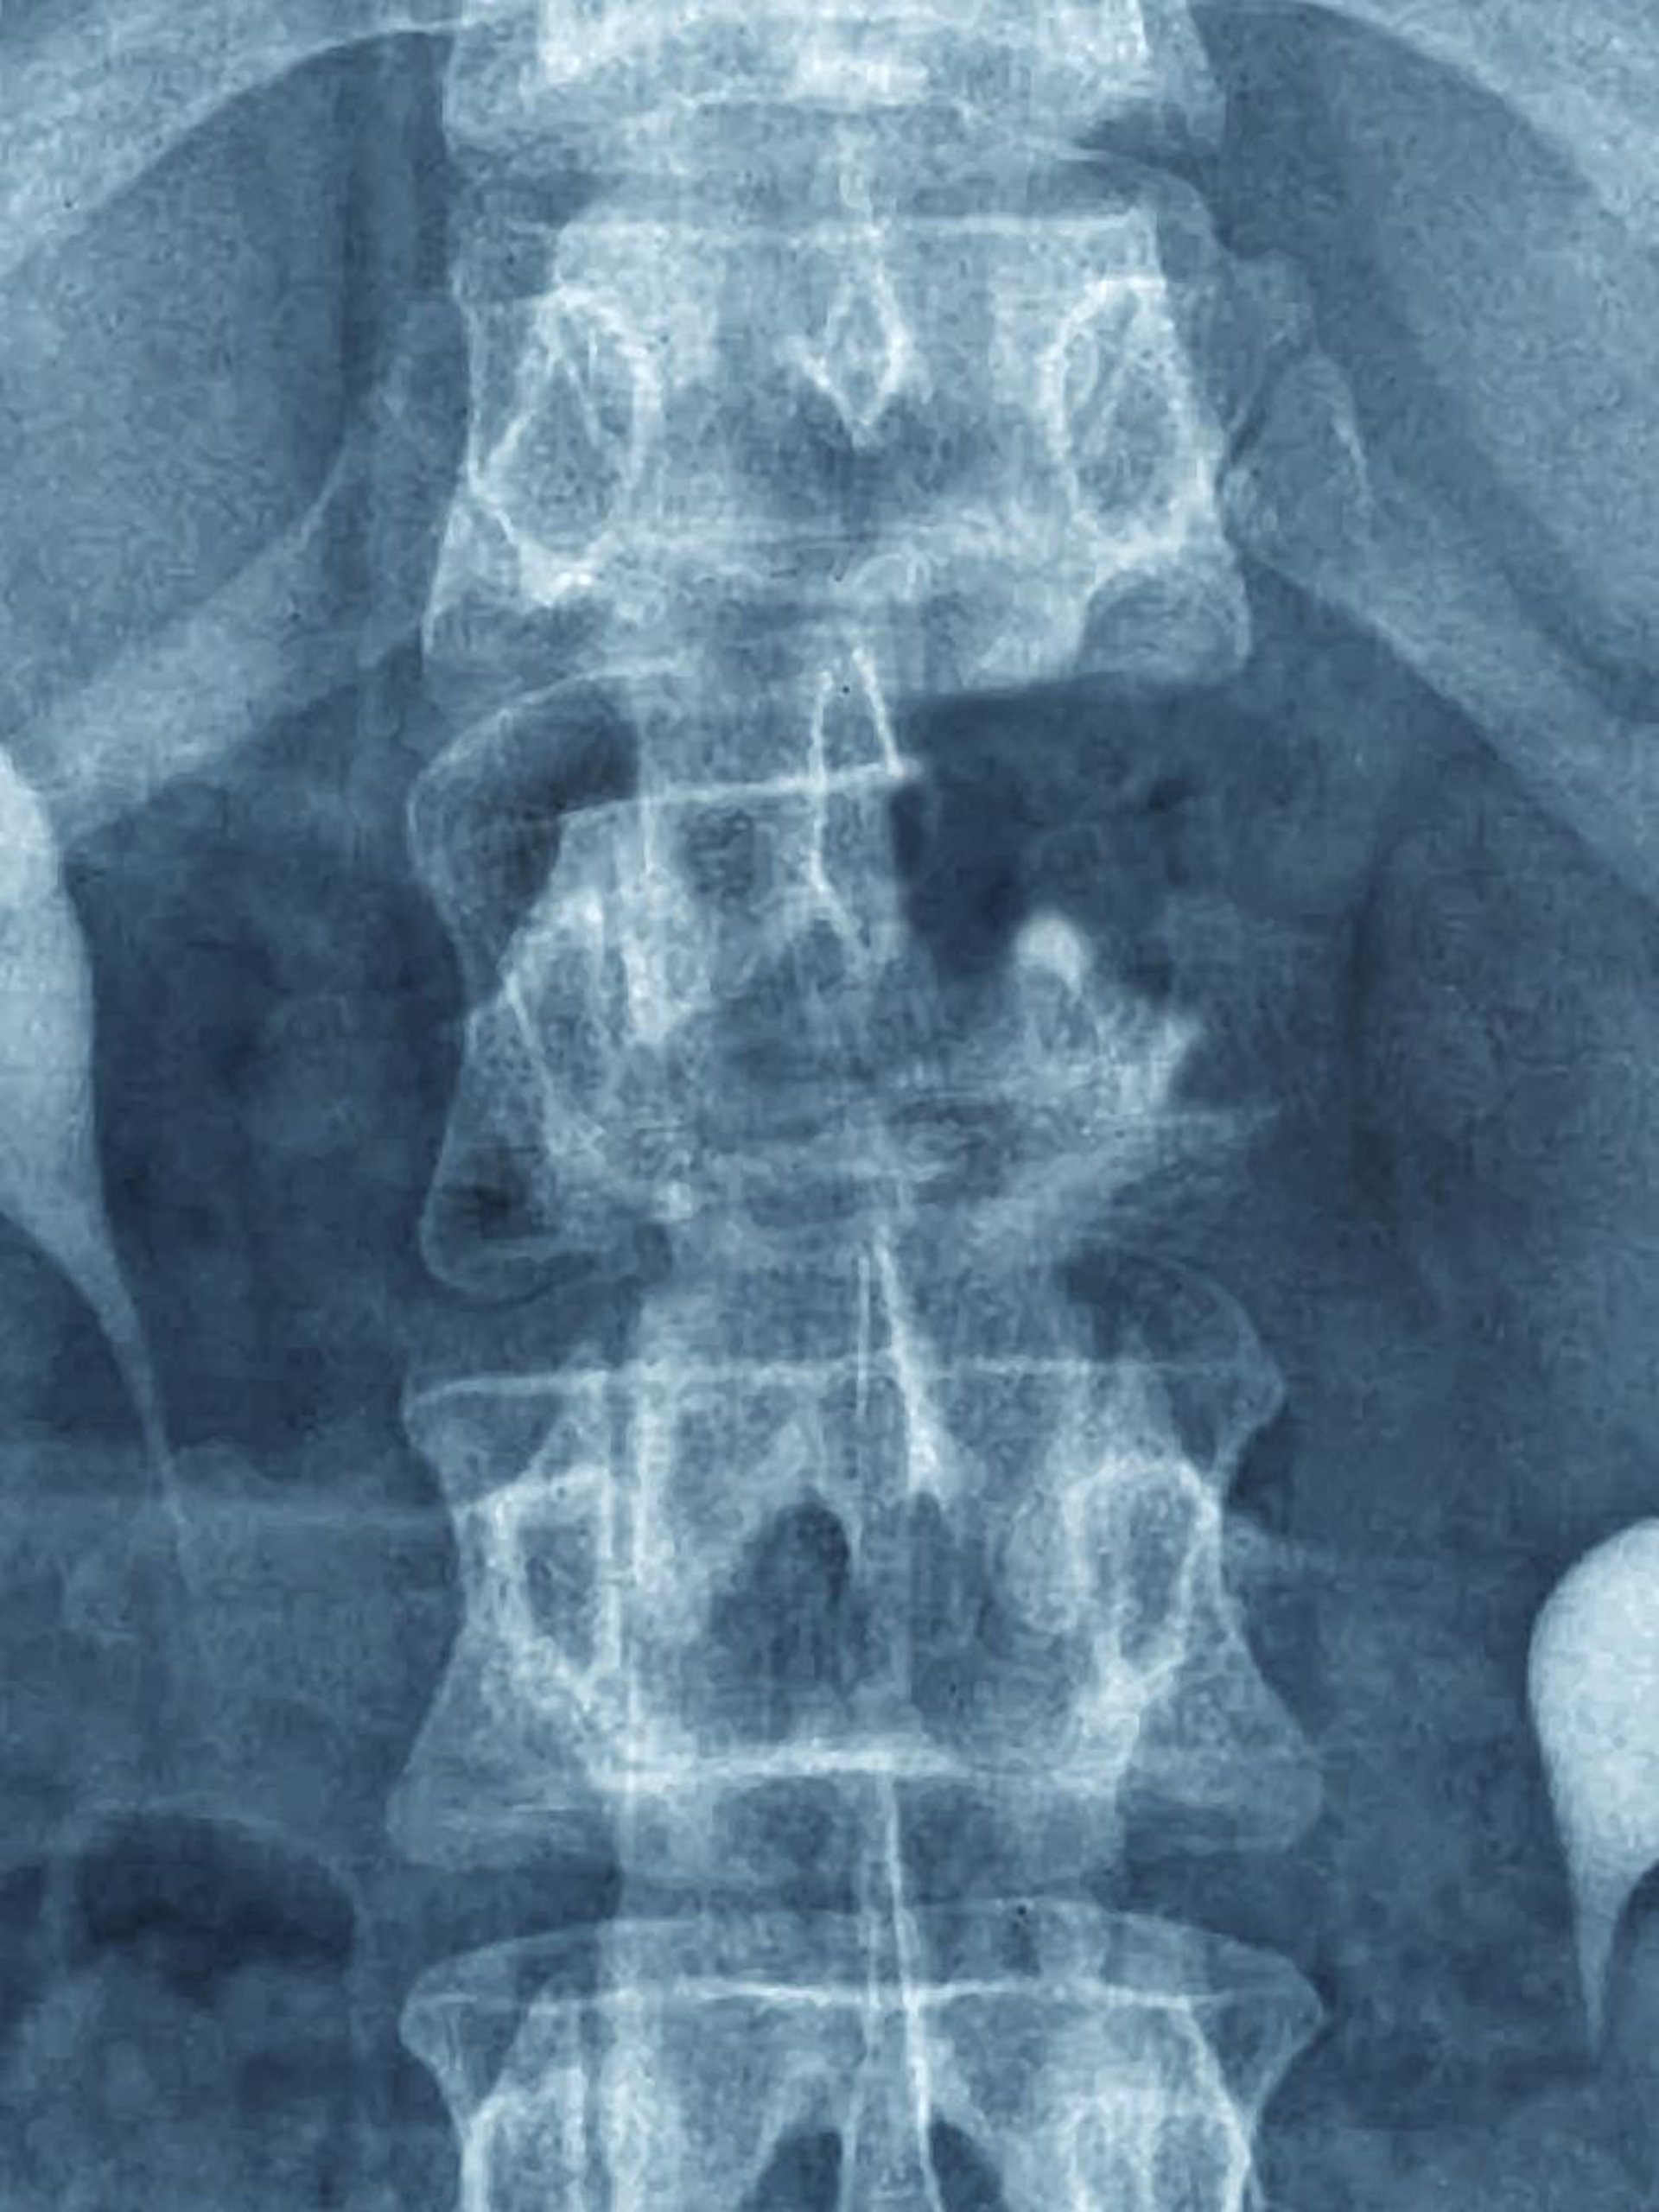

Diese Metastase ist im Röntgenbild als destruktive Läsion sichtbar, die den oberen Teil des L1-Wirbels betrifft (beachten Sie den fehlenden Pedikel).